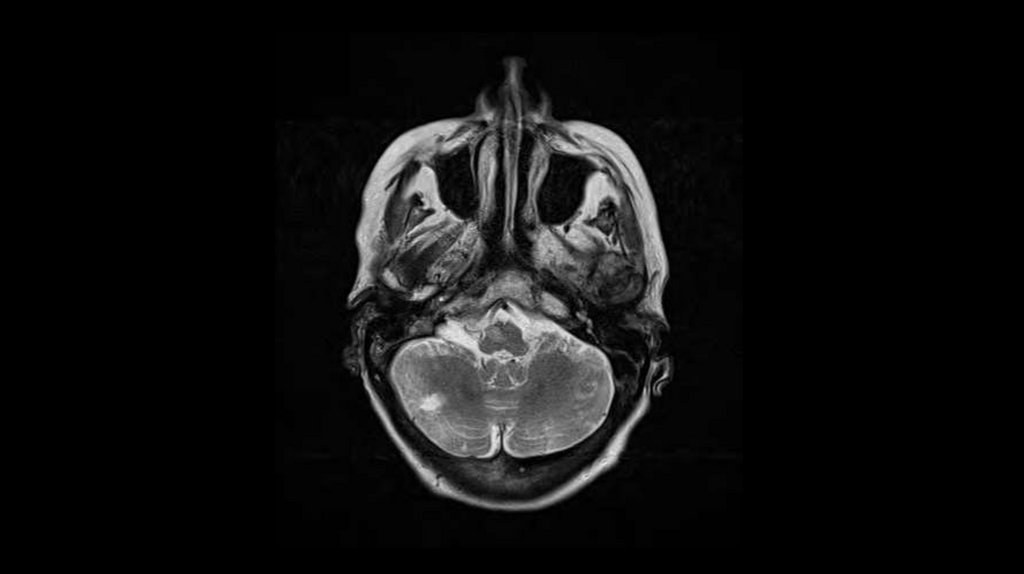

67 year-old woman

Presented with left sided

weakness

Slurred speech

Left facial droop

Double vision

BP: 210/110 mm Hg